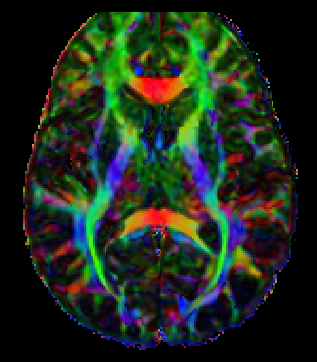

Diffusion Tensor Imaging (DTI) Explained

Diffusion tensor imaging - NeuRA Library

Diffusion Tensor Imaging (DTI)

Diffusion tensor imaging (DTI) tractograpy. The color-coding of

Diffusion Tensor Imaging (DTI) - Fiber Tracking - Imagilys

Diffusion MRI, also referred to as diffusion tensor imaging or DTI

Diffusion MRI, also referred to as diffusion tensor imaging or DTI